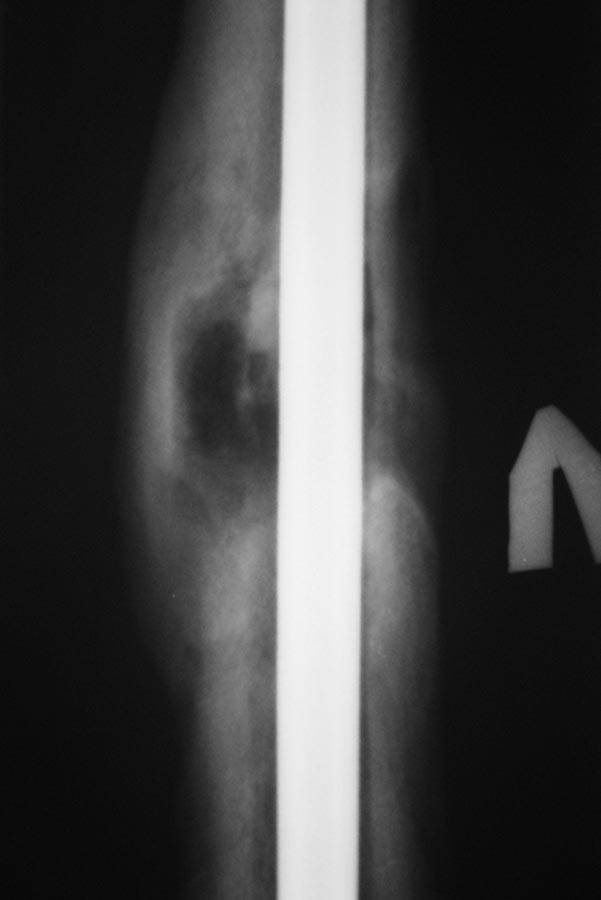

Пациент после БИОС бедренной кости.

Пациент 26 лет, около года назад получил травму в результате ДТП. По

поводу перелома диафиза бедренной кости выполнялся БИОС. Заживление ран

в области дистальных блокирующих винтов происходило вторичным

натяжением, однако, в ходе местного лечения раны зажили. Спустя 4-5 мес.

пациент обратился с болями в нижней трети бедра (проекция дистальных

блок. винтов). При RG выявлена их миграция, выполнено их удаление.

Спустя еще 4-5 мес обратился с жалобами на припухлость в

области дистального блокирования. В поликлинике сделали снимки и, с

подозрением на остеомиелит, оправили в стационар. Сегодня: местно - без

признаков инфекции. В области дистального блокирования припухлость

плотно-эластичной консистенции. При пункции получить ничего не удалось.

Лейкоциты 6,0; СОЭ - 22. СРБ-18. Температура в вечерние часы

37-37,2 Снимки представлены.